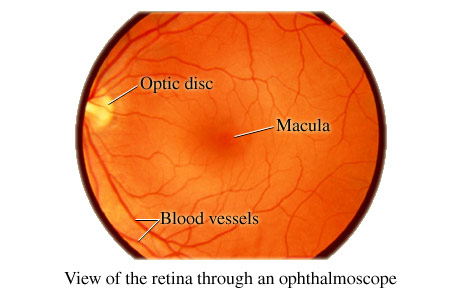

Oftalmoscopia

OFTALMOSCOPIA Oftalmoscopia este un test care permite vizualizarea structurilor din interiorul ochiului numit fund de ochi, precum si a altor structuri, cu ajutorul unui instrument de marire numit oftalmoscop siCiteste tot ... 1638 cuvinte

Dimensiune medie

+ cu poze |